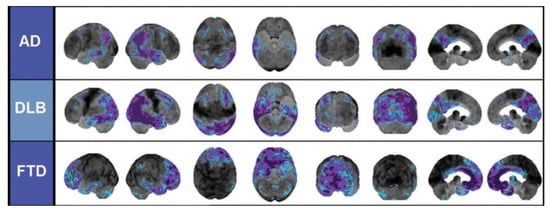

- Brown, R.K.J.; Bohnen, N.I.; Wong, K.K.; Minoshima, S.; Frey, K.A. Brain PET in Suspected Dementia: Patterns of Altered FDG Metabolism. Radiographics 2014, 34, 684–701. [Google Scholar] [CrossRef] [PubMed]